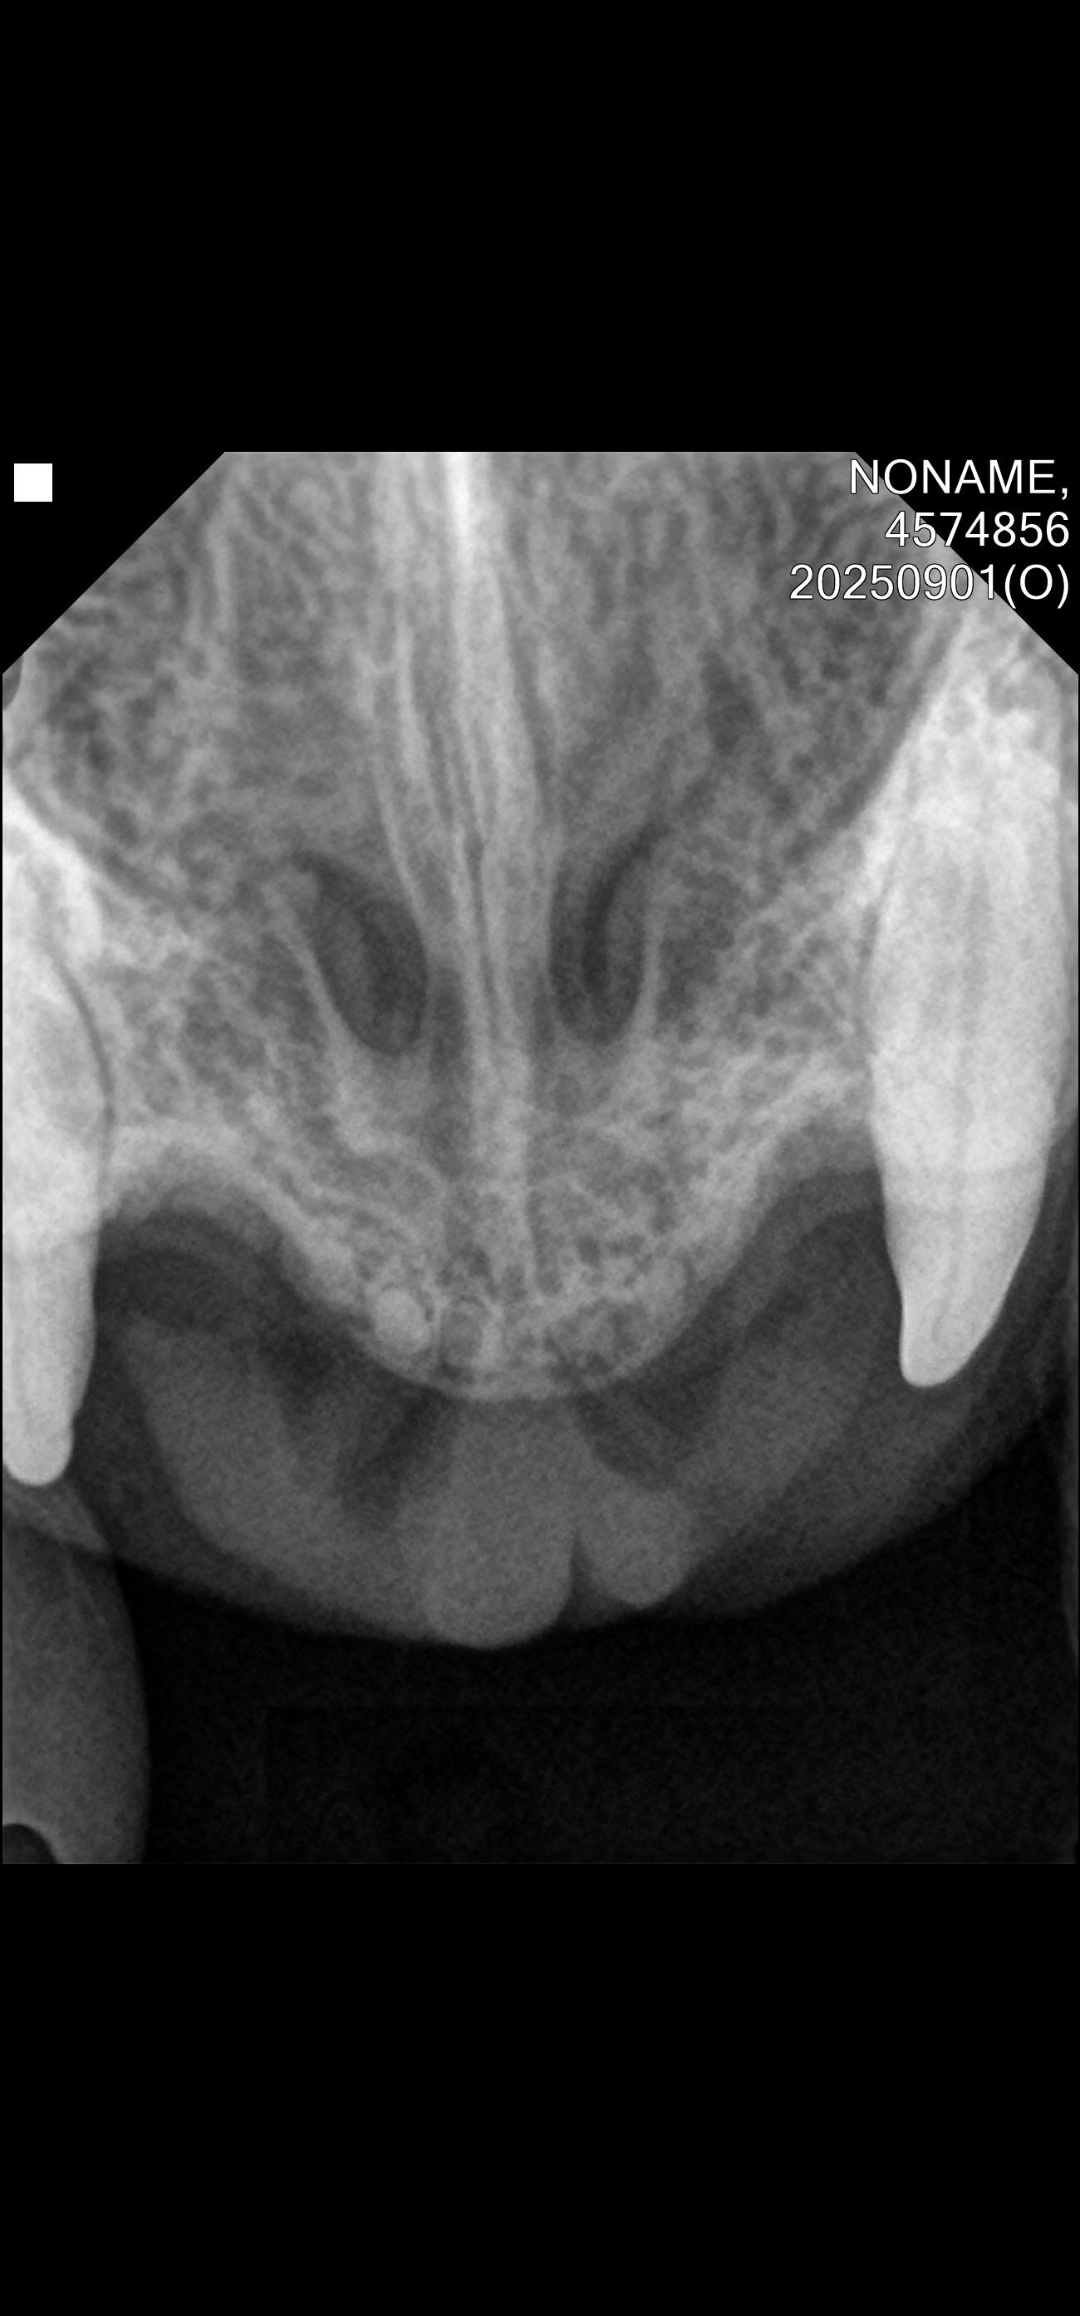

| 대상묘 병명 | 칼리시 치아흡수병변으로 인한 구내염 |

| 치료과정 | 8월31일에 구조하여 병원에 데려갔고 병원에서 발치 수술을 진행했습니다. 발치 당시 혈액검사 상으로 빈혈 수치가 있고 황달이 있어서 수술 후에 2주 입원시켰습니다. 앞에 송곳니는 치아흡수병변 소견도 있고 현재로는 염증이 없거나 살짝 있는 걸로 보여 발치하지 않고 어금니와 다른 이빨들만 발치했습니다. 송곳니를 제외한 앞니는 이미 빠져있었고 송곳니도 치아흡수병변 증상으로 발치할 경우 턱뼈가 부러질 수도 있어서 발치를 하지 않으셨다고 합니다. 나이가 들면서 치주질환과 충치가 생긴 줄 알았는데 칼리시로 인한 구내염이고 목구멍과 혀에까지 궤양이 있었습니다. 목구멍은 레이저치료를 했으나 혀는 레이저 치료가 위험해서 하지 못 했습니다. 수술 후에 잘 먹으면 황달은 없어진다고 해서 입원시켜서 상태를 지켜봤는데 다행이 잘 먹고 잘 잤다고 합니다. 염증이 너무 심해서 입원해 있을 동안 계속 투약했습니다. 2주 입원 후에 방사하려고 했으나 아직 너무 말라있고 았던 기간이 오래되기도 해서 좀 더 데리고 있기로 결정했습니다. 기력이 다시 떨어지는 것 같기도 하고 다시 잘 안 먹으려고 하기도 해서 2주간 실내에서 더 케어하면서 상태를 관찰한 후에 방사하려고 합니다. 스테로이드제제를 2주 이상 투약해서 휴지가를 가졌다가 다시 먹여보려고 합니다. |